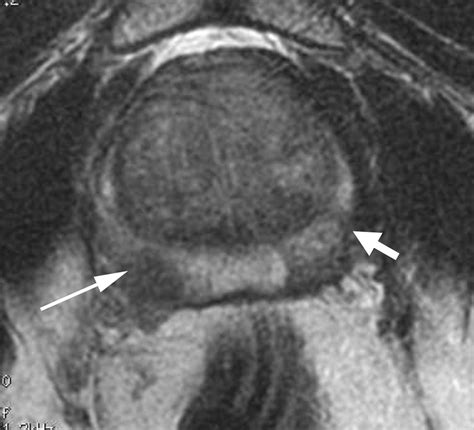

• T2-weighted imaging: Provides high-resolution anatomical images, allowing the radiologist to see the shape and size of the prostate clearly.

• Diffusion-weighted imaging (DWI): Measures the movement of water molecules within the tissue; cancerous cells, being more densely packed, restrict this movement, which shows up as a “bright spot” on the scan.

• Dynamic Contrast-Enhanced (DCE) imaging: Involves the injection of a contrast dye to observe how blood flows into the tissue, as tumors often exhibit distinct blood vessel patterns compared to normal tissue.

The combination of these sequences creates a comprehensive view that significantly increases the sensitivity and specificity of the diagnosis.